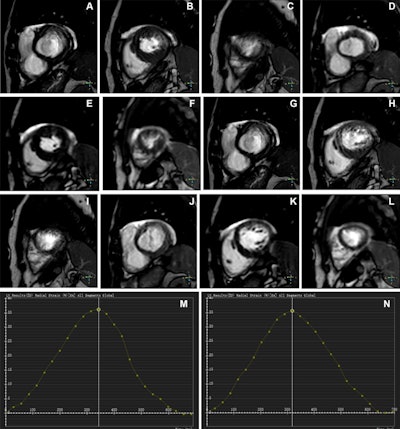

Representative images of participants with difficulty with breath holding and arrhythmia. In the lower right corner of A–L, the position coordinates of the images are marked. Short-axis (SA) view images in the end-systole (A–F) and end-diastole (G–L) phases in participants with atrial fibrillation. (A–C, G–I) Balanced steady-state free precession (bSSFP) cardiac cine. (D–F, J–L) Deep learning–enhanced compressed sensing (AI-CS) single-shot cardiac cine. In contrast to AI-CS single-shot cardiac cine, endocardial contours were challenging to identify on conventional segmented cine in midventricular and apical sections. (M) Line graph of time curve during the whole cardiac cycle obtained from bSSFP cardiac cine. (N) Line graph of time curve during the whole cardiac cycle obtained from AI-CS single-shot cardiac cine. LV = left ventricle; 2D = two-dimensional.Representative images of participants with difficulty with breath holding and arrhythmia. In the lower right corner of A–L, the position coordinates of the images are marked. Short-axis (SA) view images in the end-systole (A–F) and end-diastole (G–L) phases in participants with atrial fibrillation. (A–C, G–I) Balanced steady-state free precession (bSSFP) cardiac cine. (D–F, J–L) Deep learning–enhanced compressed sensing (AI-CS) single-shot cardiac cine. In contrast to AI-CS single-shot cardiac cine, endocardial contours were challenging to identify on conventional segmented cine in midventricular and apical sections. (M) Line graph of time curve during the whole cardiac cycle obtained from bSSFP cardiac cine. (N) Line graph of time curve during the whole cardiac cycle obtained from AI-CS single-shot cardiac cine. LV = left ventricle; 2D = two-dimensional.RSNA